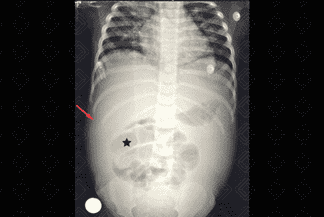

• Apagamento da gordura pré-peritoneal: Paciente com quadro de ascite e oclusão intestinal por brida (figura 2 abaixo). Para mais informações, acesse Obstrução Intestinal;

ccc Figura 2. Créditos: Dra. Elazir Mota - Rio de Janeiro/RJ

Descrição da figura 2: Criança com quadro sugestivo de oclusão intestinal pós-abordagem cirúrgica prévia. Na radiografia de abdome em AP observamos as alças medializadas no abdome (asterisco) e o apagamento da gordura pré-peritoneal, sugerindo presença de líquido livre (seta vermelha). Para mais informações, acesse Obstrução Intestinal.

Texto alternativo para a imagem Figura 3. Créditos: Dra. Elazir Mota - Rio de Janeiro/RJ

Descrição da figura 3: Presença de imagem radiopaca no oco pélvico à direita (seta vermelha). Estudo foi complementado com ultrassonografia que evidenciou cálculo no ureter direito. Para mais informações, acesse Nefrolitíase.